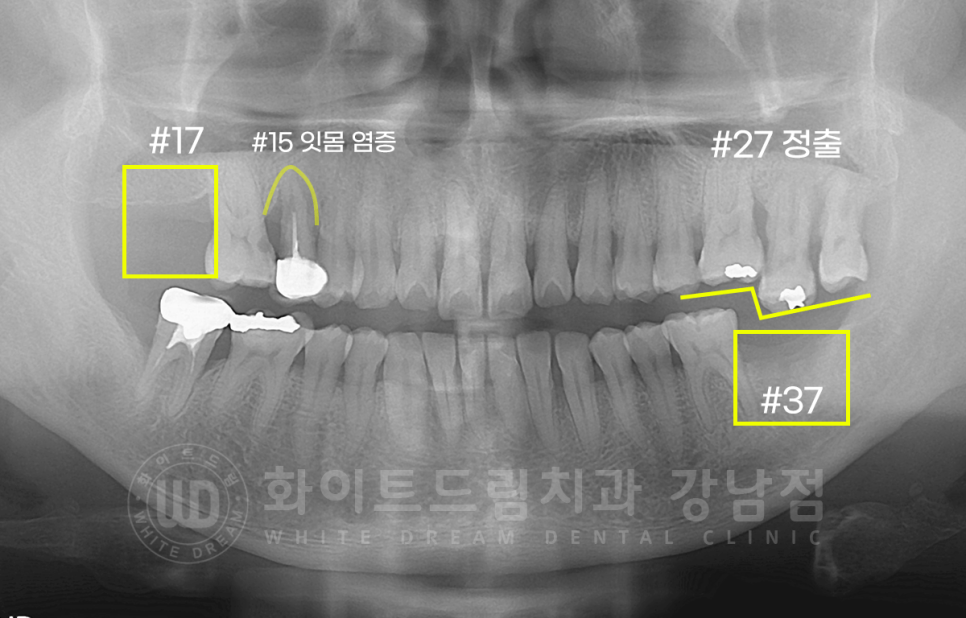

환자분의 초진 x-ray입니다.

서초동 어금니 임플란트 치료 전 / x-ray

10번대 : 17번 치아 상실, 15번 치아 잇몸 염증, 16번 치아 인접면 충치

20번대 : 37번 치아 상실로 27번 치아 정출

30번대 : 37번 치아 상실

의 문제가 있으셨고, 문제 치아들은 모두 발치 후 임플란트를 식립하기로 했습니다.